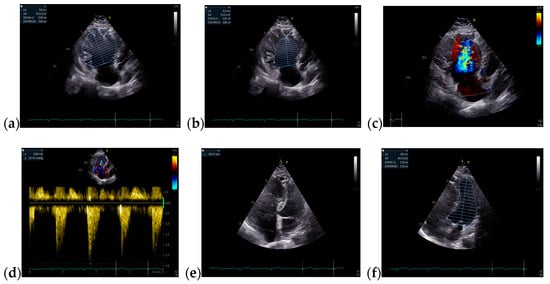

The TTE performed on admission showed a non-dilated left ventricle with an ejection fraction (EF) of 51% (using Simpson’s method), dilated right chambers, mild functional tricuspid regurgitation, mild pulmonary hypertension, tricuspid annular plane systolic excursion of 19 mm, inferior vena cava (IVC) with 18 mm diameter, and respiratory variability greater than 50%. The TTE raised the suspicion of ASD with significant hemodynamic shunt (Qp/Qs = 2.24) (Figure 2 and Figure 3).

Figure 2.

TTE on admission: (a) Parasternal long axis view with enlarged diameter of RV; (b) Apical 4-chamber view, tricuspid continuous wave Doppler flow, with a maximum RV-RA gradient of 32.33 mmHg; (c) Apical 4-chamber view, EF = 51% (Simpson’s method); Abbreviations: TTE—transthoracic echocardiography; RV—right ventricle; RA—right atrium; EF—ejection fraction.

Figure 3.

TTE on admission: (a) Parasternal long axis view measuring LVOT diameter = 2 cm; (b) Parasternal short axis view: Pulmonic VTI = 20.3 cm; (c) Parasternal short axis view: pulmonary artery trunk = 2.2 cm; (d) Apical 5 chamber view: Systemic VTI = 17.6 cm, Qp/Qs = 2.24; Abbreviations: TTE—transthoracic echocardiography; LVOT—left ventricle outflow tract; VTI—velocity-time integral.